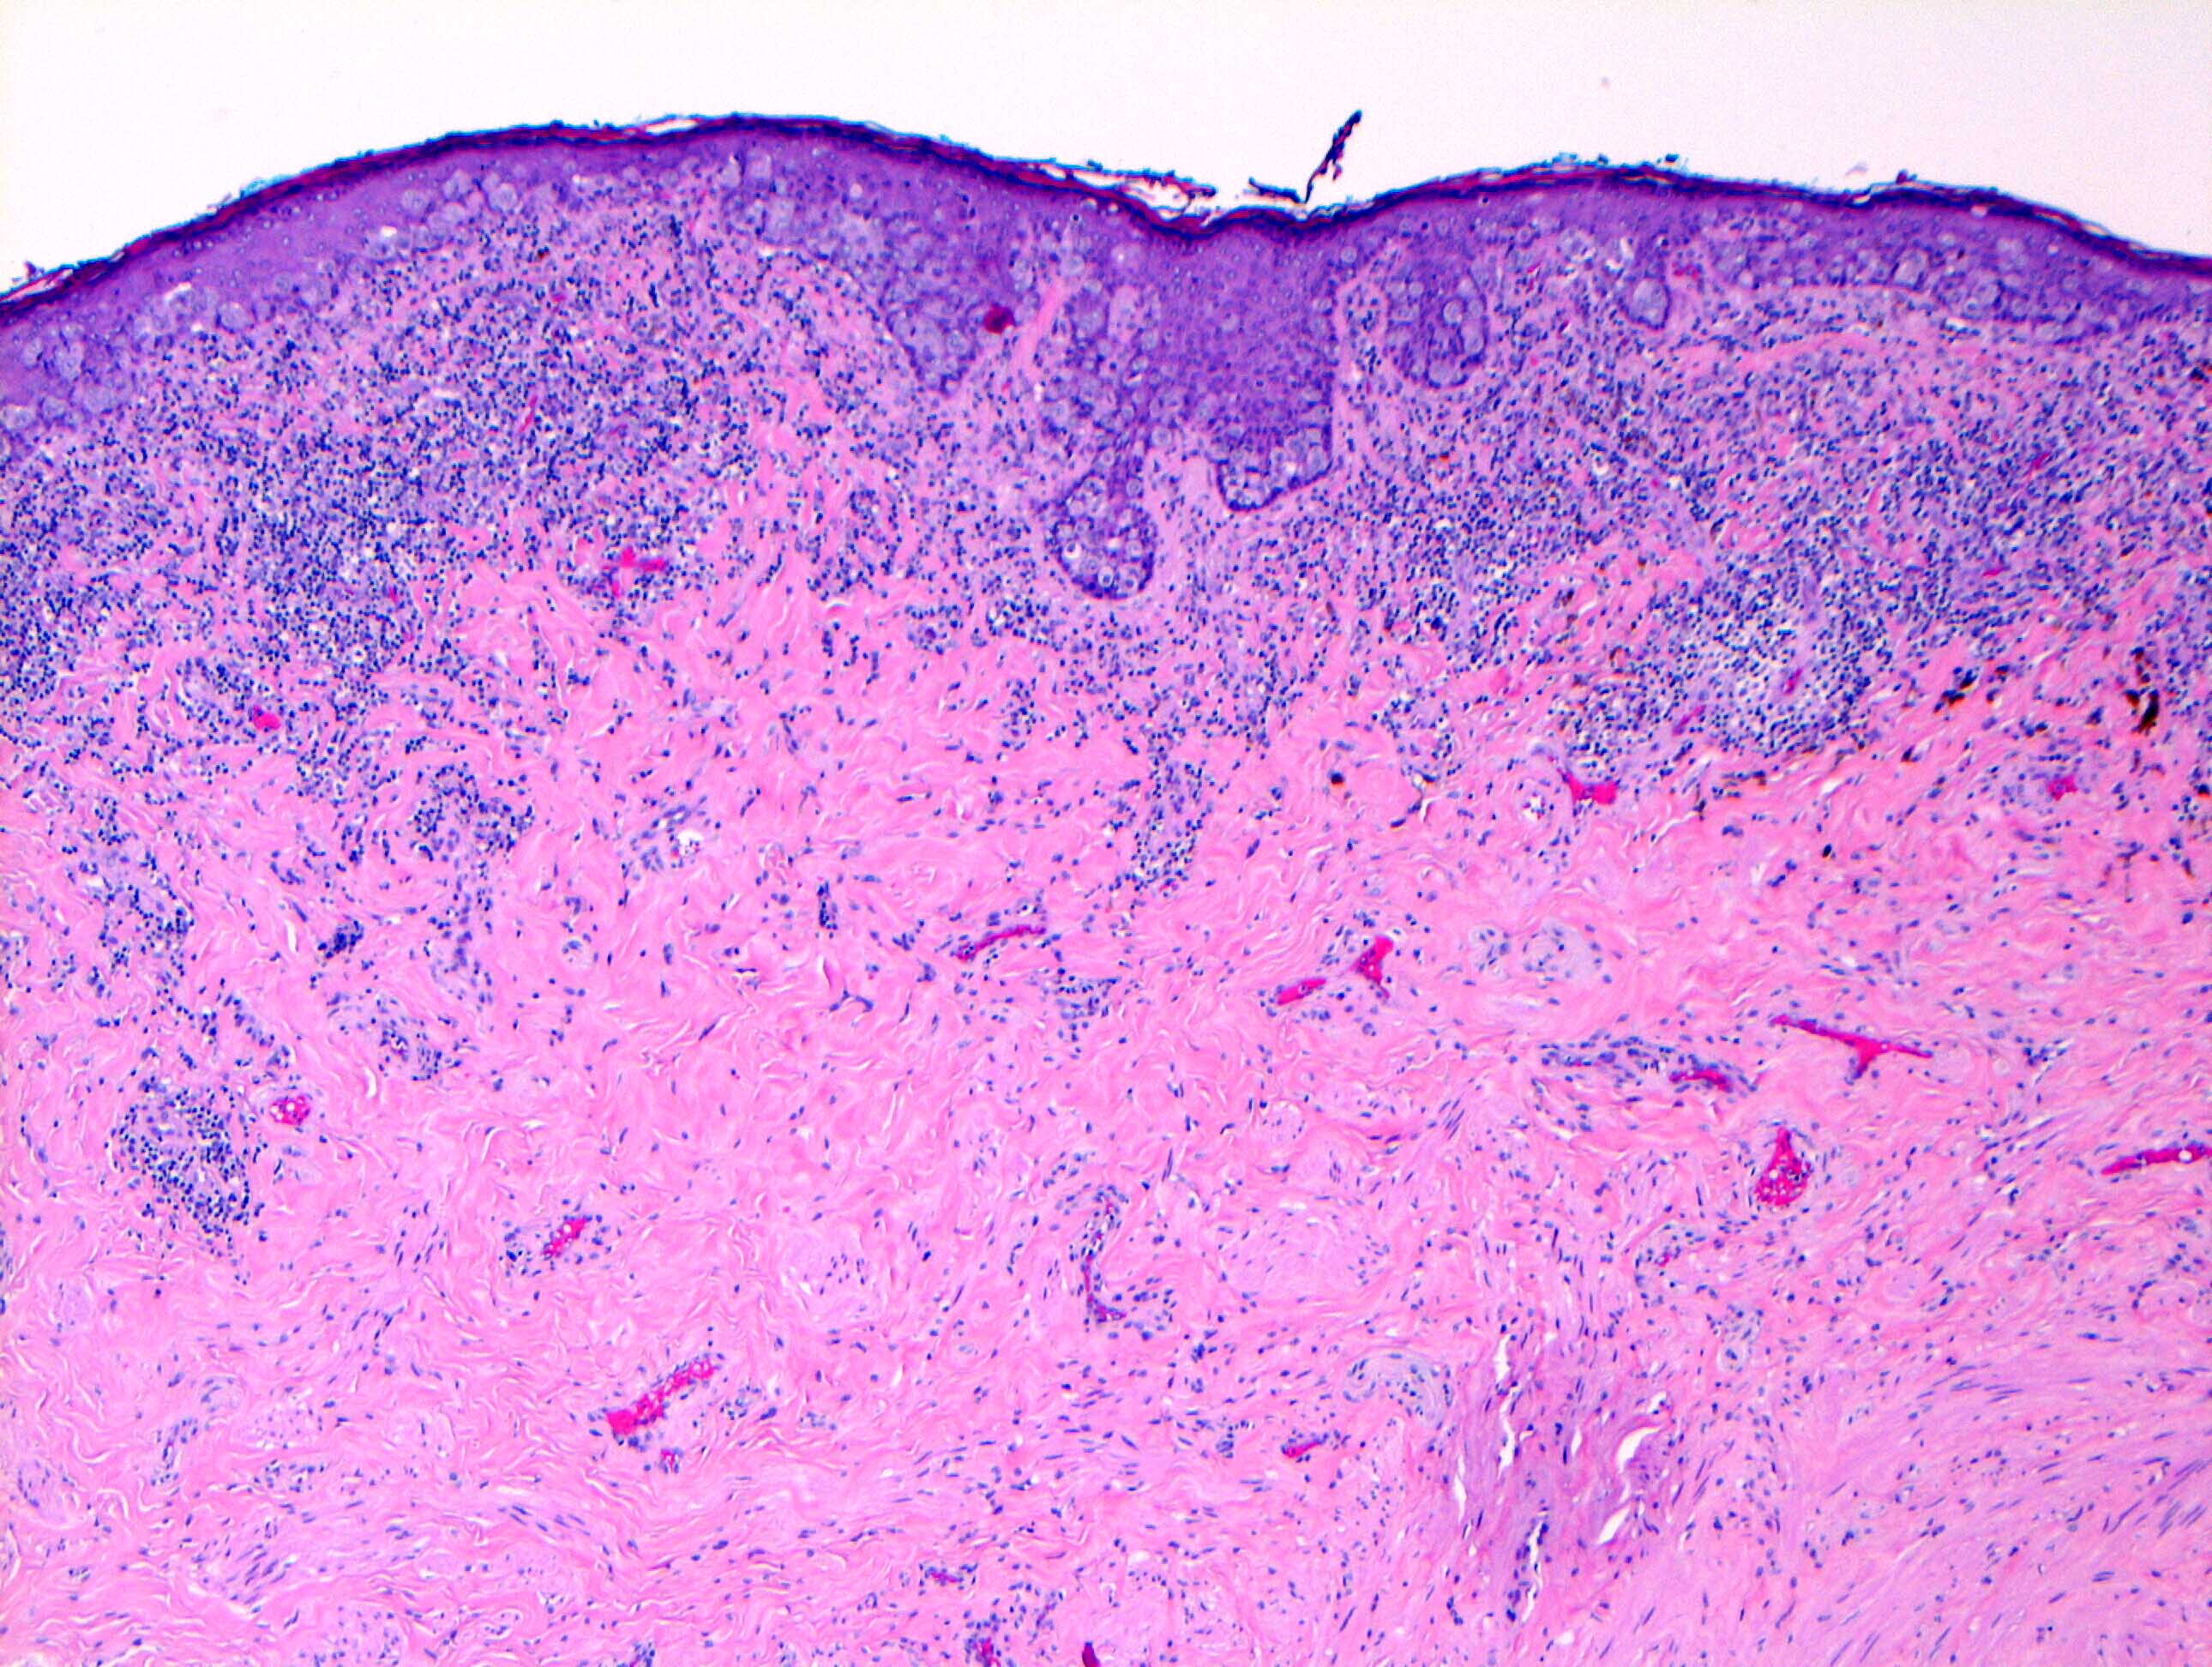

Microscopic (histologic) description

- Single cells or clusters of cells spread throughout the epidermis

- Cells have abundant pale cytoplasm, large irregular nuclei with prominent nucleoli

- Underlying dermis may have chronic inflammation

- Epidermis with hyperkeratosis and possibly ulceration

- Florid cases can show gland formation

- Paget cells may phagocytose melanin, mimicking melanocytes

- Underlying carcinoma is most commonly high grade invasive carcinoma of no special type (NST; 53 - 64%) or DCIS (24 - 43%) (Histopathology 2020;77:181)

Microscopic (histologic) images

Contributed by Anna Biernacka, M.D., Ph.D. and Mary Ann Gimenez Sanders, M.D, Ph.D.